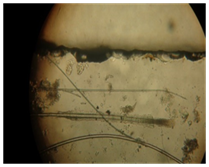

Figure 9 Microscopic structure.